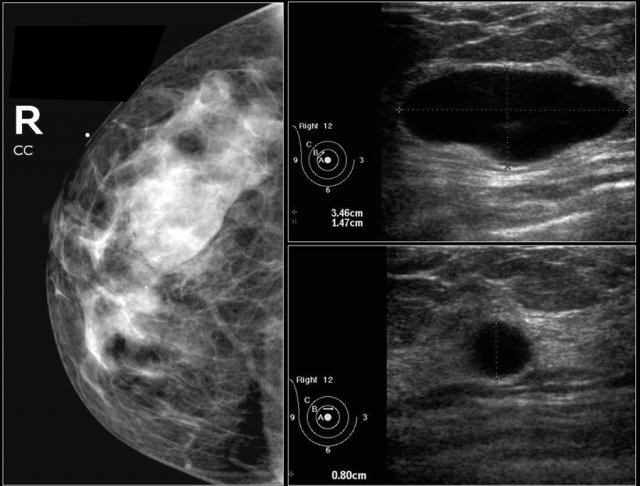

First study the images and describe the findings.

Then continue reading.

The findings are:

• Mass with irregular shape.

• Spiculated margin.

• High density.

• Ultrasound also shows irregular shape with indistinct margin.

This mass is categorized as BI-RADS 5.